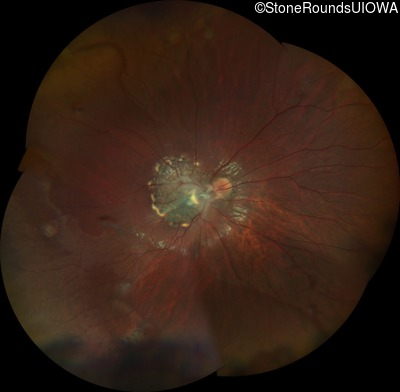

This 9 year old male was noted to have some crossing of his eyes at 2 months of age and the eye exam which followed identified a retinal lesion in the right eye. When he was six years old an epiretinal membrane was noted in his left eye. Two years later it was decided that it was a thin hamartoma in that eye as well. He underwent neuroimaging at age 7 which identified bilateral acoustic neuromas.

| Age at visit: 10 years |

| Age at visit: 11 years |

| Age at visit: 14 years |